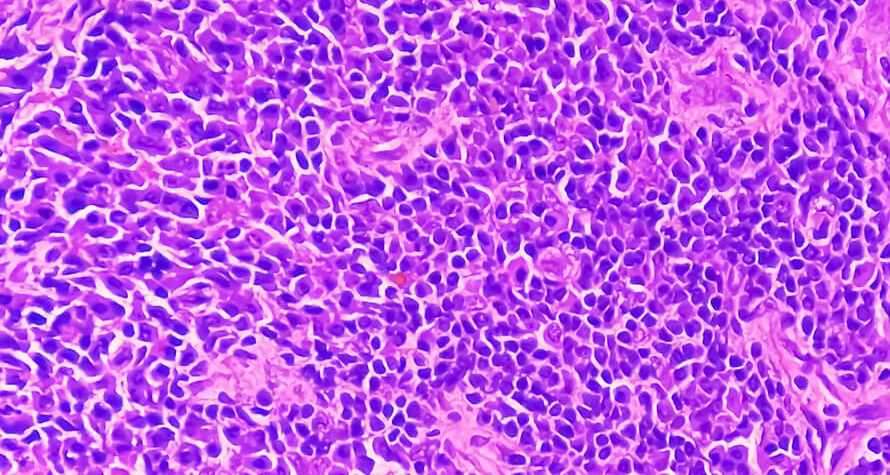

Problem:

Pathologists who are unfamiliar with whole slide imaging technology

Solution:

Easily find "whole slide imaging technology" experineced remote digital pathologist

IKET Digital Pathologist Networking Platform, will give a great opportunity to work with digital pathology experienced pathologist who has knowledge on whole slide imaging technology worldwide remotely